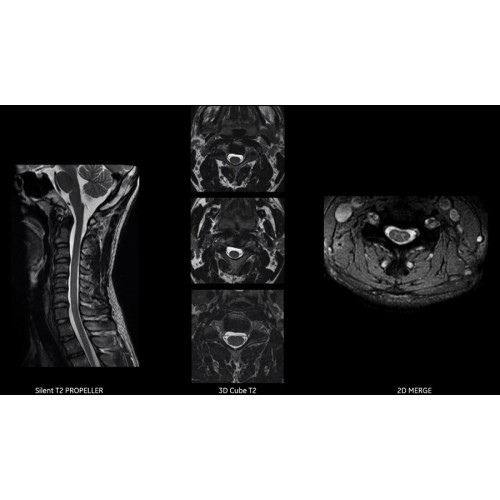

Благодаря революционному программному пакету Silent Suite уровень шума снижается до 77 дБ, что всего на 3 дБ выше уровня окружающей среды. Программный пакет Silent Suite теперь включает полный пакет приложений для исследования ЦНС (T1, T2 FLAIR, DWI10, МРА). Кроме того, мы расширили возможности визуализации Silent за пределы ЦНС для исследований скелетно-мышечной системы и позвоночника. Silent Suite – платформа, содержащая в себе все импульсные последовательности для бесшумного сканирования.